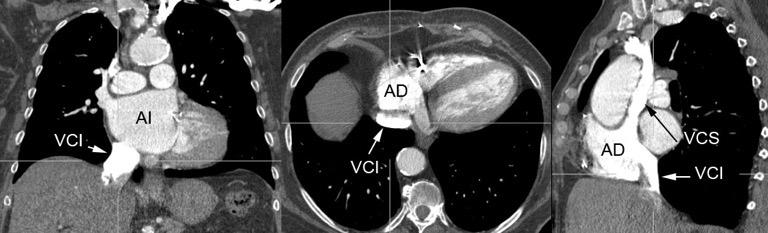

34. ENF. TORACOABDOMINAL. ANEURISMA INTRACRURAL

Aneurisma aórtico intracrural

/Restrepo CS et al. The diaphragmatic crura and retrocrural space: normal imaging appearance, variants, and pathologic conditions. Radiographics 2008